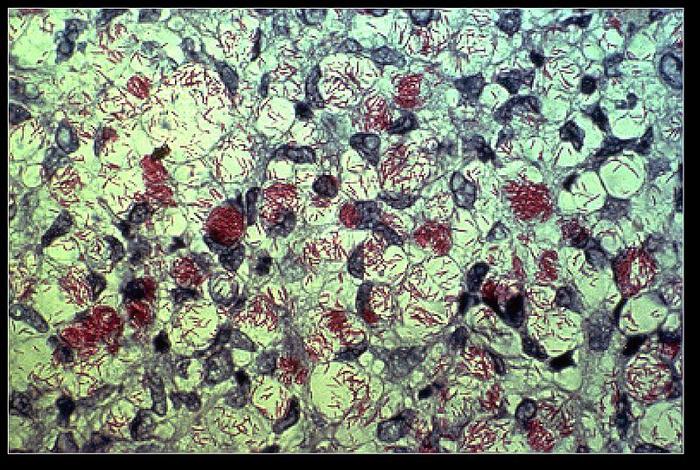

Journée mondiale des lépreux : la maladie des extrêmes guérissable et évitable résiste encore et toujours

La lèpre est une maladie infectieuse chronique, l’une des plus mal perçues par la population.